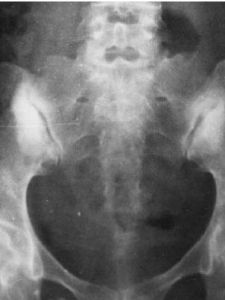

陽性。3.退變性骶髂關節炎

X線平片上顯示關節退變,視病程不同而出現退行性變的各期表現,以增生及骨刺為主。治療方法